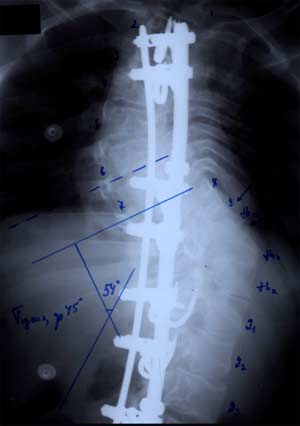

Работы

велись и продолжают вестись по двум

направлениям: первое - это совершенствование

корректора и методики операции, наиболее

простой и безопасной, позволяющей

оперировать детей на ранних сроках

развития деформации. Второй - разработка

конструкции и методики операции тяжелых

степеней сколиоза. С накоплением опыта

изменился наш взгляд на постоянный

динамический эффект корректора,

создаваемый конструкциями. В настоящее

время он рассматривается как отрицательный

при малом числе блоков крепления пластин

корректора Если же используется принцип

фиксации пластин, который использовал

А.А. Гайдуков, то в ближайший и отдаленный

послеоперационный периоды мы наблюдаем

нарастание коррекции. Сама же коррекция

сколиотической деформации сегодня

выполняться интраоперационно, а

конструкция выполняет роль фиксатора

достигнутой коррекции. Главным

достоинством конструкции и метода

является то, что в послеоперационном

периоде не происходит ограничения роста

ребенка.

Само оперативное вмешательство требует

строжайшего соблюдения технологической

дисциплины, использование специального

инструментария и, естественно, специально

изготовленных пластин и деталей

крепления. Импровизации при операциях

на позвоночнике недопустимы. Все

оперативное вмешательство занимает от

2 до 3 часов.